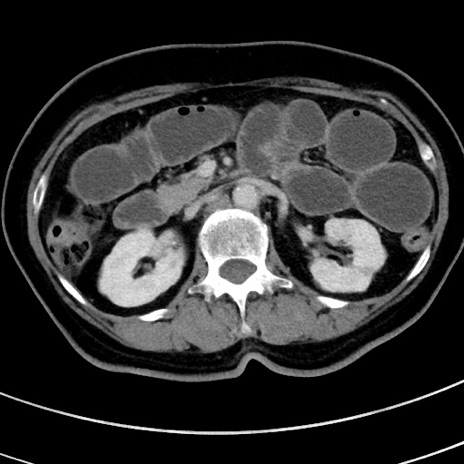

冠状断像

【症例】 60歳代女性

【主訴】むかつき、みぞおちの痛み

【現病歴】3日前よりむかつきがあり、食事がとれない。

【既往歴】糖尿病

【身体所見】発熱なし、心窩部圧痛軽度あるも、腹膜刺激症状なし。

【データ】WBC 7400、CRP 1.92